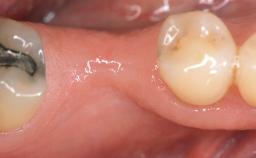

A 30-year-old woman was referred by her general dentist for evaluation of an esthetic complication related to previous implant treatment for congenitally missing maxillary lateral incisors. The patient’s chief complaint was the inadequate esthetic appearance of her smile. The case demonstrates the use of a combined approach to achieve optimal results. Two different flap designs - a tunnel technique and a coronally advanced flap - are employed based on the surgical objectives for the affected site.